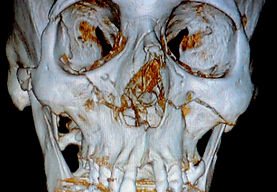

TRAUMA FACIAL

El cirujano oral y maxilofacial se encarga de la resolución de las lesiones traumáticas de la región maxilofacial, atiende las fracturas de los maxilares y de los huesos faciales mediante diversas técnicas, entre ellas la reducción abierta o cerrada de las fracturas, con o sin colocación de material de osteosíntesis.